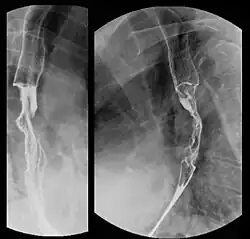

Eine Bariumsulfat-Röntgenuntersuchung während des Schluckvorgangs erlaubt es, Flüssigkeit zu beobachten, die in der Speiseröhre nach unten transportiert wird. Dies kann helfen, Größe, Verfassung und Lage der Geschwulst zu beobachten.